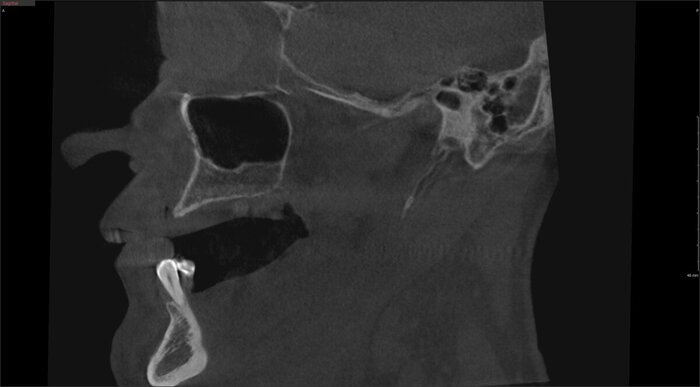

А вот как выглядел наш любимый, быстрый воск:

Постановка на воске

Разница - в первом варианте зубы не из стандартного набора, а те, что пациенту подходят больше. С этим прототипом можно даже пожить какое-то время, попривыкать к нему. Понять, что нравится, а что не особо.